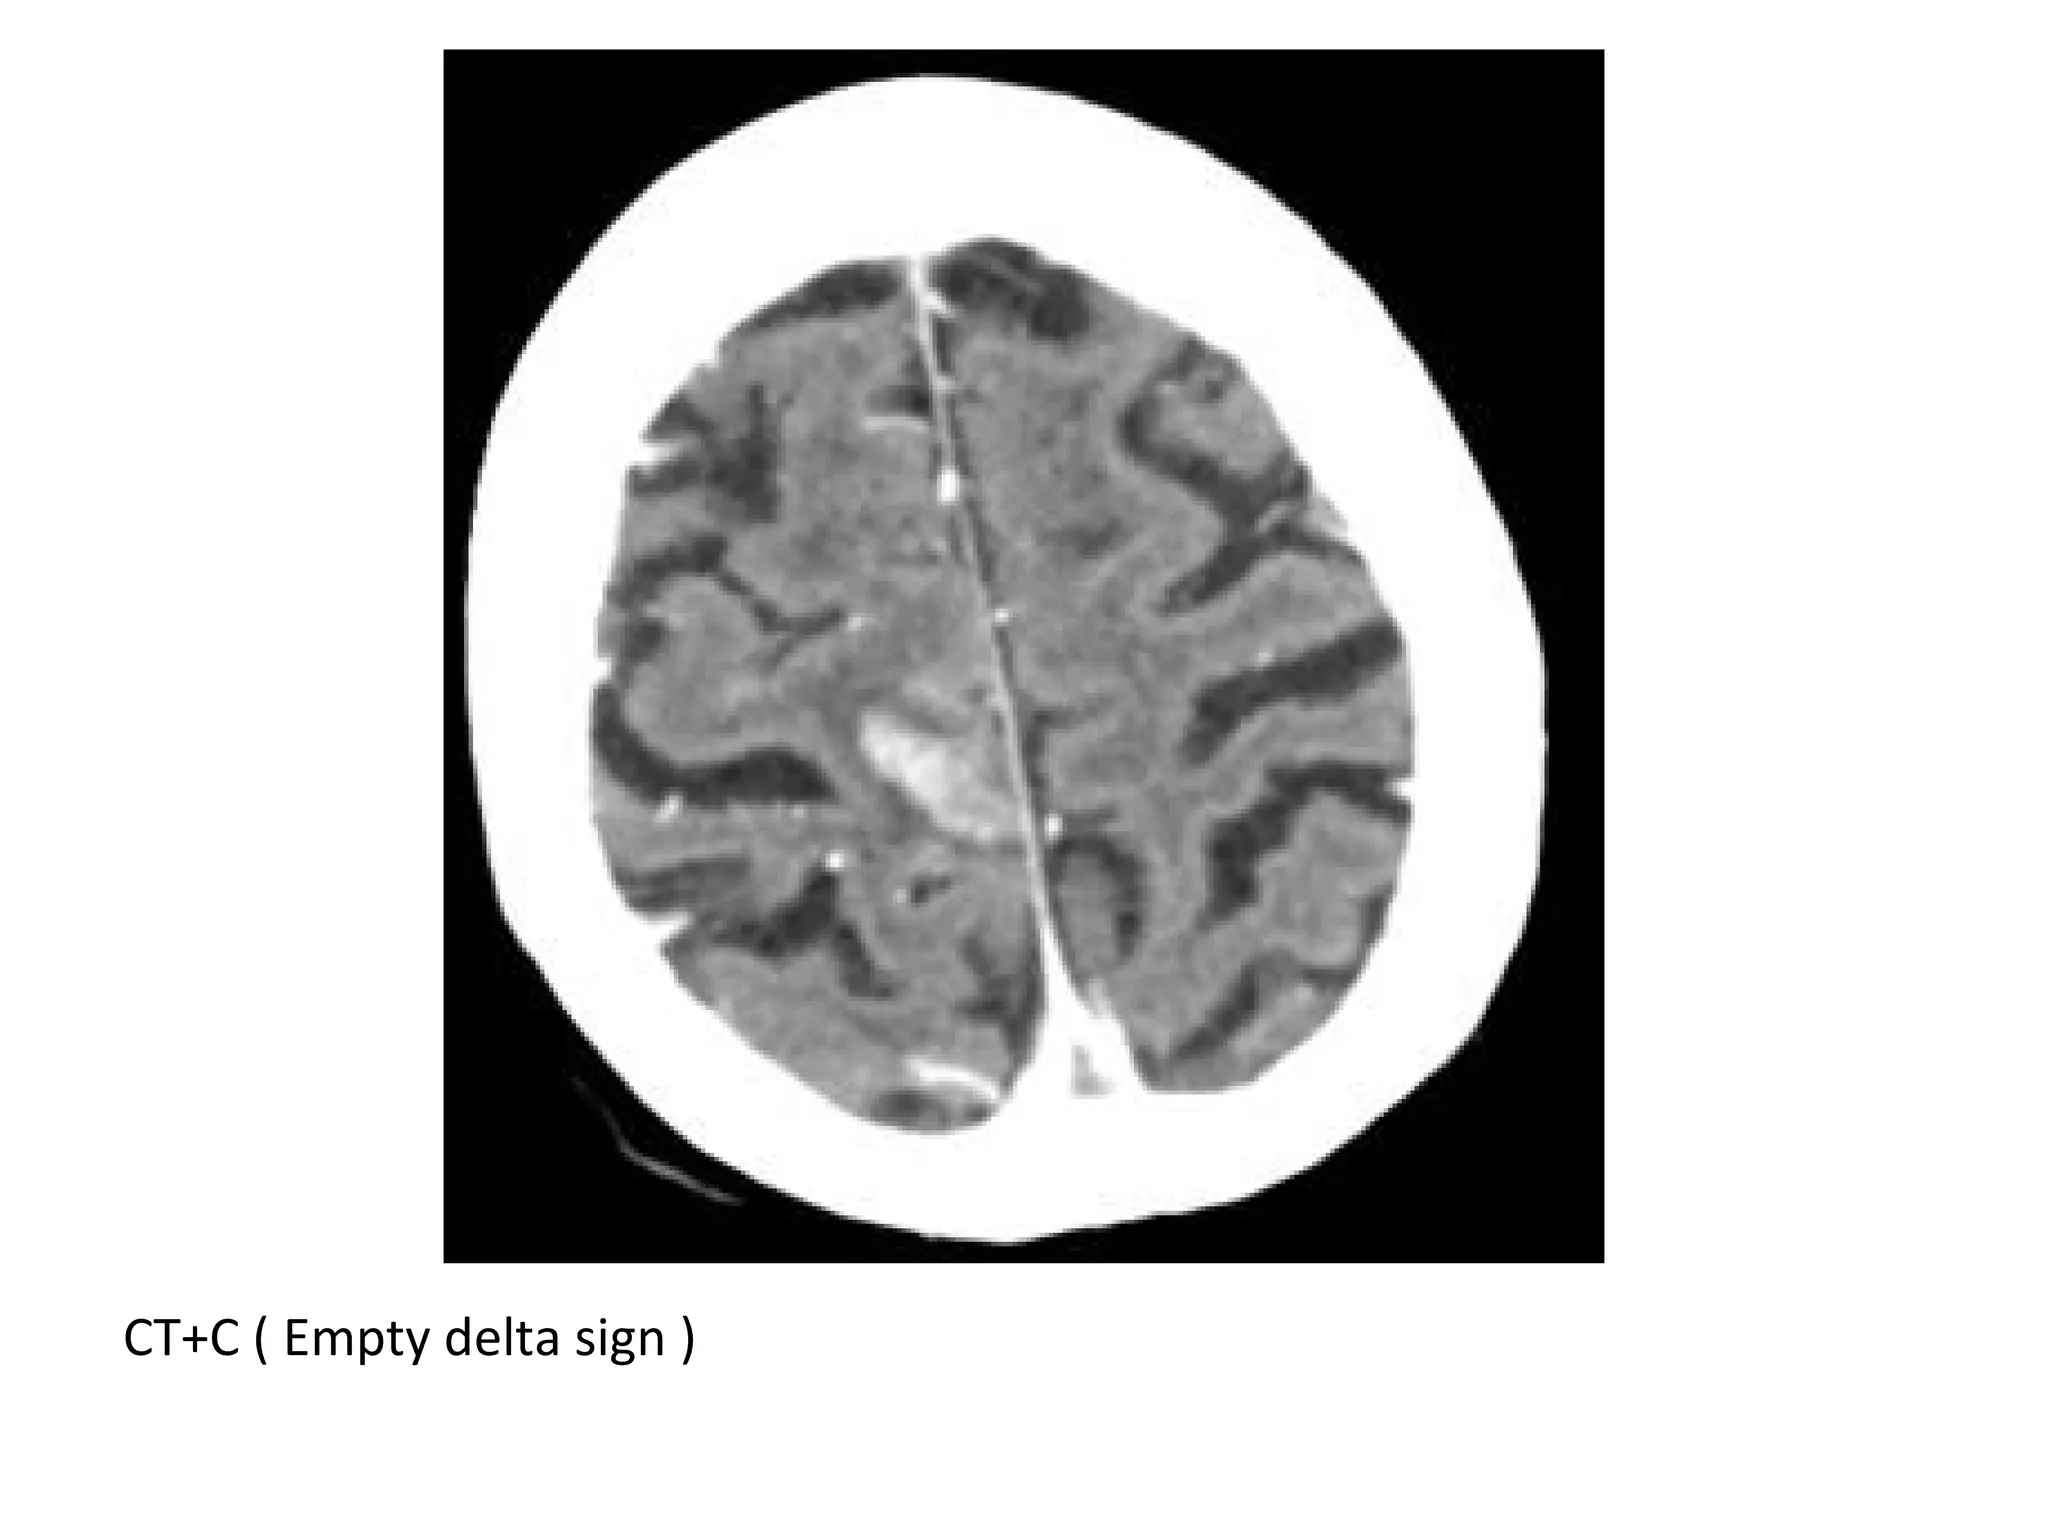

2-Empty Delta sign :

*The sign consists of a triangular area of enhancement

with a relatively low-attenuating center which is the

thrombosed sinus

*In early thrombosis the empty delta sign may be absent

and you will have to rely on non-visualization of the

thrombosed vein on the CECT

*The sign may be absent after two months due to

recanalization within the thrombus

CT+C : Empty delta sign due to thrombosis of the SSS

CTV (Empty delta sign)

CT+C (Empty delta sign)

CT+C ( Empty delta sign )